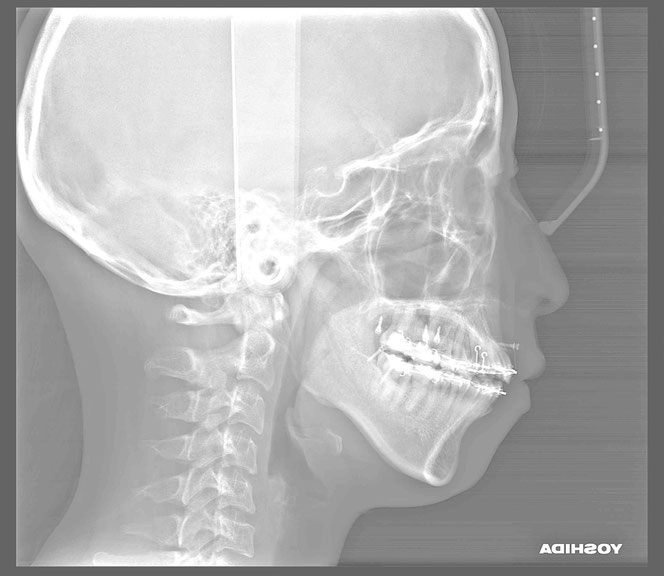

治療後の変化

再生治療により、

2~3ミリ下がっていた歯ぐきが回復。

歯の長さが自然なバランスに戻り、

厚みのある丈夫な歯ぐきが再建されました。

奥歯6本の再生治療を行ったケースでは、

虫歯予防という機能面の改善も期待できます。